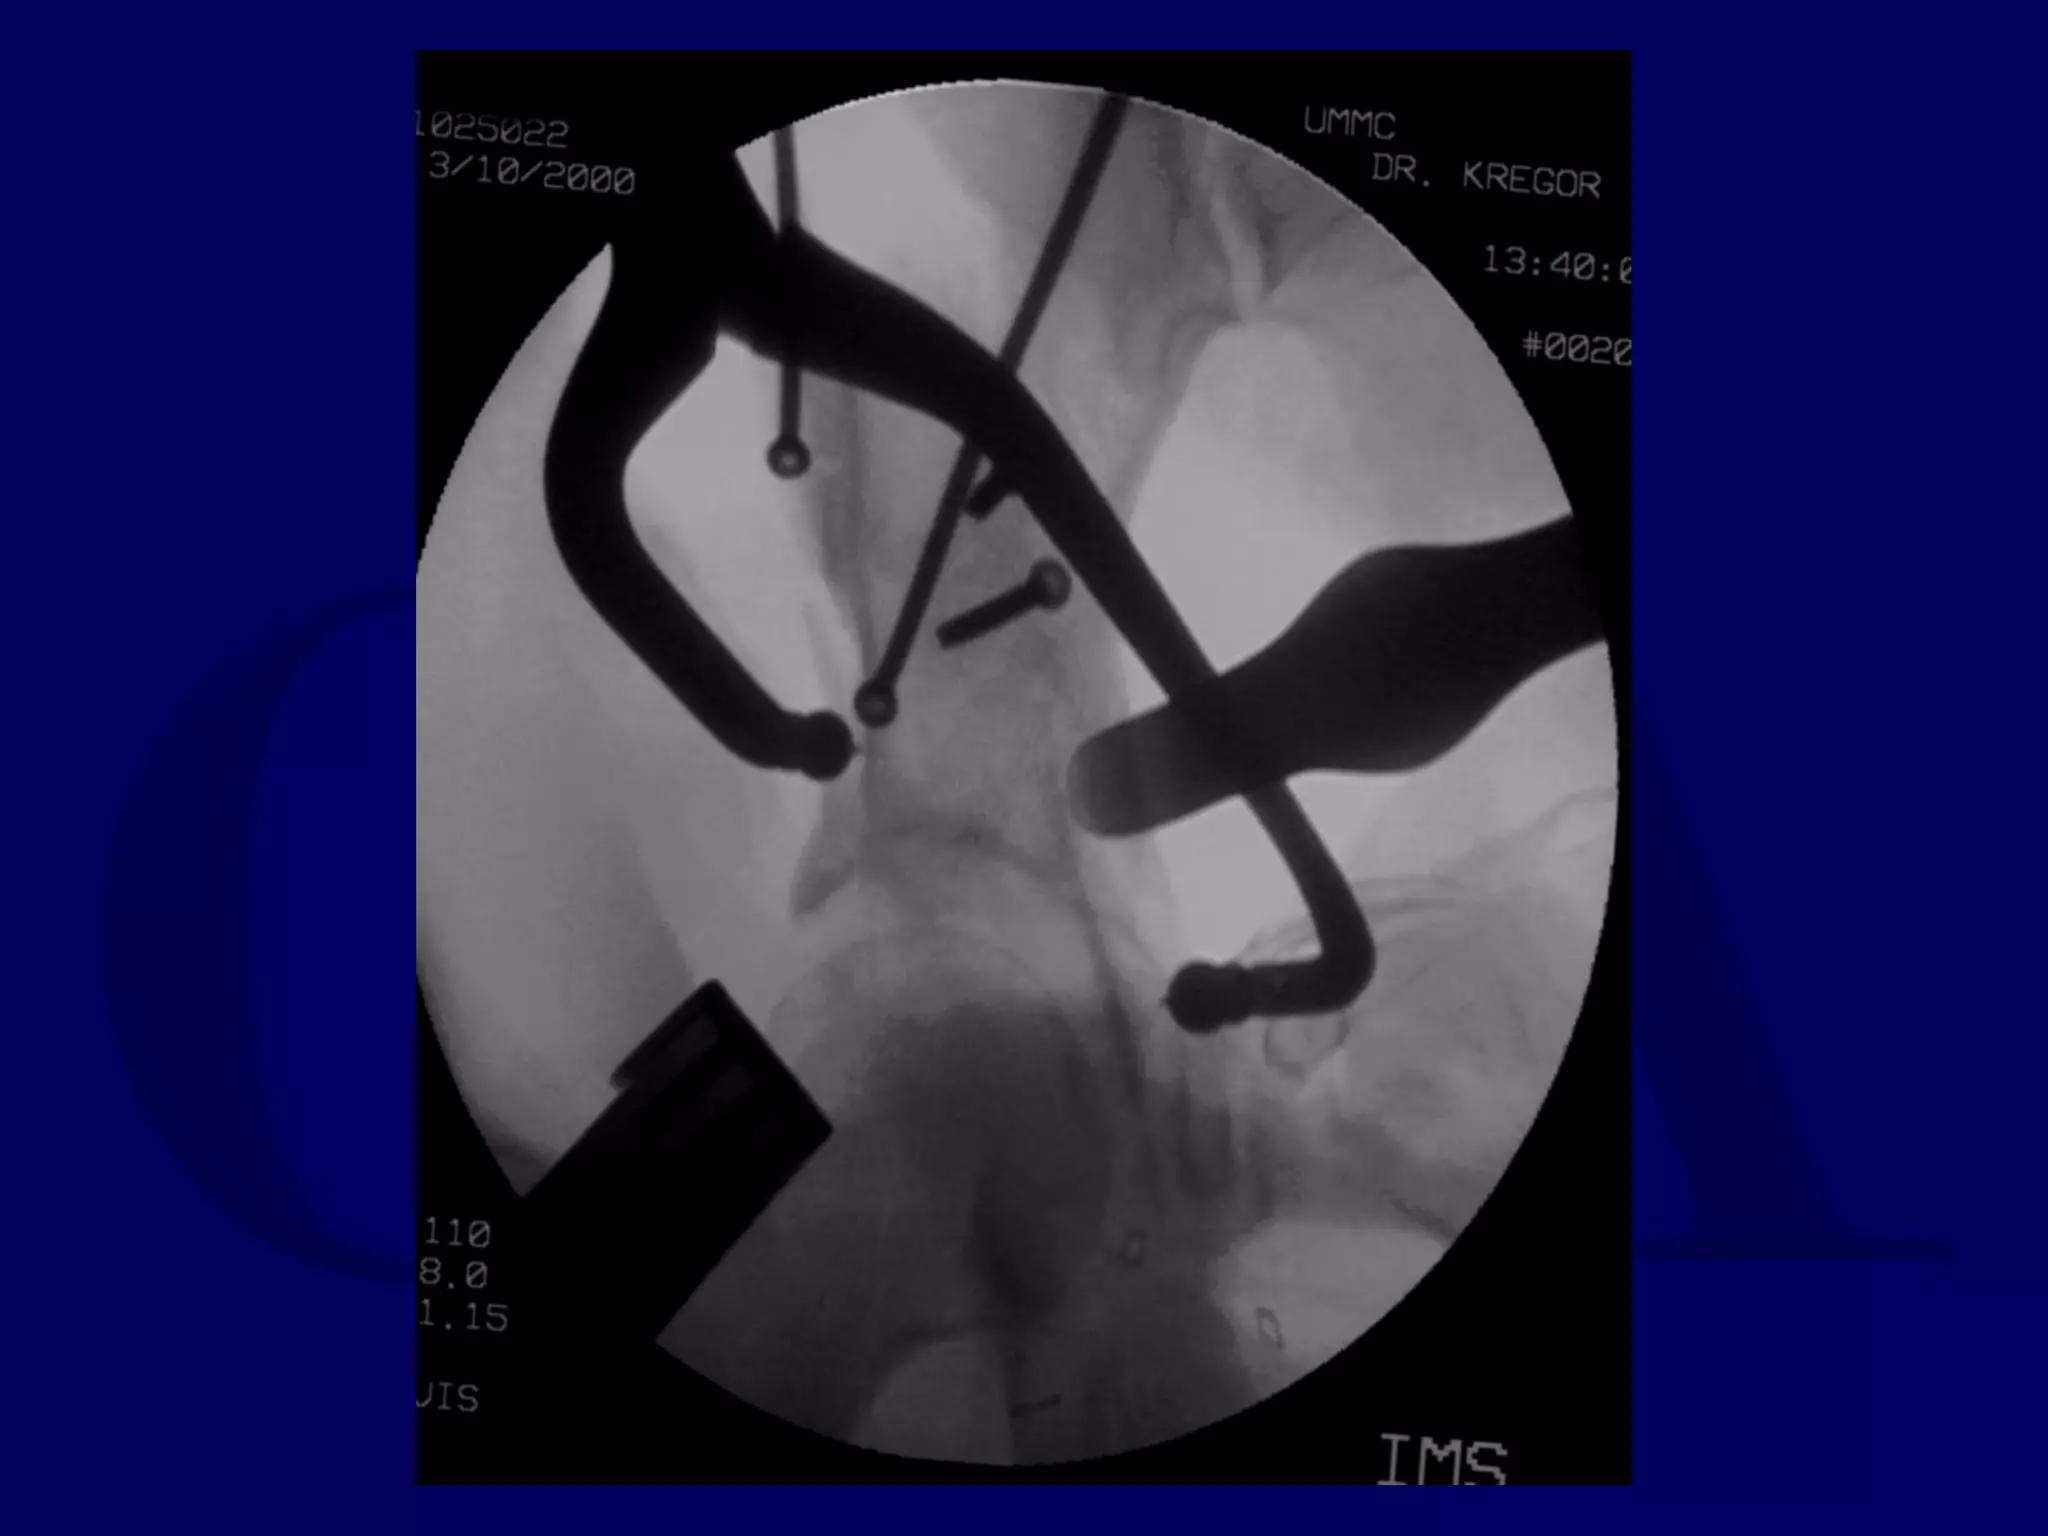

Completion of Iliac Fracture

Reduction of Anterior Column

to Intact Ilium

Reduction of Posterior Column

INTACT ILIUM

R.C. 00.03.10